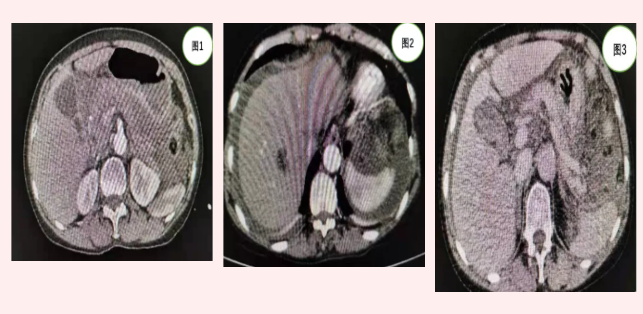

患者張某入院時,急診行全腹CT(見圖1)等相關(guān)檢查發(fā)現(xiàn)上腹部包塊但未見明顯肝脾破裂及腹腔積液。由于患者外傷,病情隨時可能加重,主管醫(yī)師張浩杰嚴密觀察病情時,患者腹痛加重,血紅蛋白進行性下降,立即復(fù)查上腹部增強CT(見圖2、3)發(fā)現(xiàn)腹腔大量積液。

急診外科亞?聘敝魅螐埲A甫查看患者后考慮腹腔臟器破裂遲發(fā)出血可能,行腹腔穿刺抽出不凝血,證實了腹腔臟器破裂出血診斷。立即給予手術(shù)備血并完善術(shù)前準備,急診行剖腹探查術(shù)。